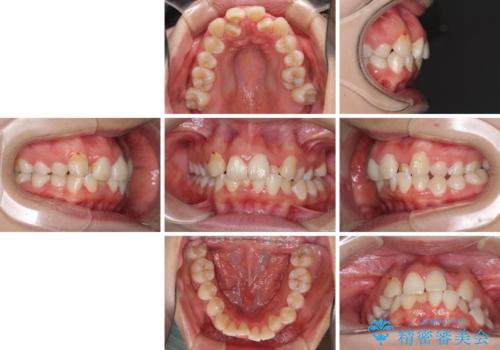

- 骨格的な咬み合わせのズレ、前歯のデコボコとクロスバイトを気にして来院された患者様です。

口元の突出感が若干あり口が閉じにくく、デコボコが強いため、上下左右の小臼歯計4歯を抜歯し、ワイヤー装置による矯正治療を行うこととしました。

また、舌の突出癖が強く、下顎前歯が前方に押し広げられる可能性が高いため、舌癖の改善を継続的に行うよう指示しました。